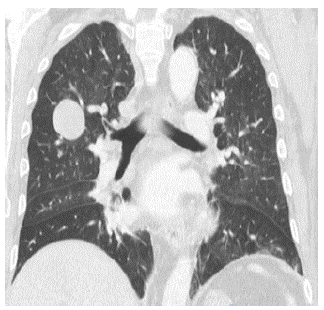

A magnetic resonance (MRI) of the abdomen showed a large retroperitoneal mass of 19x18x13cm, which displaced the ascending colon, the second duodenal portion, and the head of the pancreas. The lesion had a heterogeneous signal pattern in sequences with T1 and T2 information, predominantly hyperintense, with heterogeneous enhancement after administration of contrast medium. These findings suggested solid lesion with associated hemorrhagic residuals and multiple focal liver lesions that had a similar pattern (Figure 2).

Contrast abdomen MRI.

Figure 2: Contrast abdomen MRI.

Source: Document obtained during the study.

The MRI showed heterogeneous signal on T1 and T2 secondary to the hemorrhage and necrosis areas in the tumor. 6 In the case presented here, the abdominal magnetic resonance showed a lesion of 19x18cm, which was highly suggestive of malignant neoplasm, as well as heterogeneous signal on T1 and T2, which together with the lesions observed in lung and liver, led to the diagnosis of tumor recurrence by ACC.